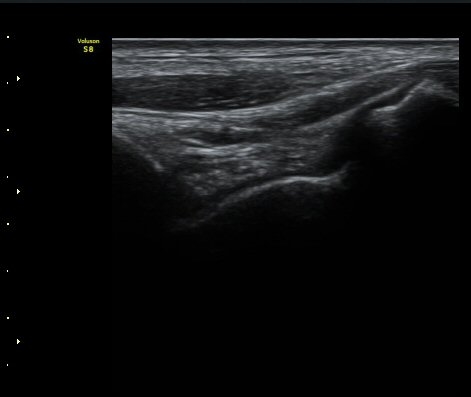

¹ß¸ñ°üÀý Á¾´Ü¸é°Ë»ç¿¡¼­ °üÀý³» ¼ö¾×Àú·ù°¡ °üÂûµÈ´Ù(±×¸² 1).

±×¸²1) ¹ß¸ñ°üÀý Á¾´Ü¸é°Ë»ç±Û